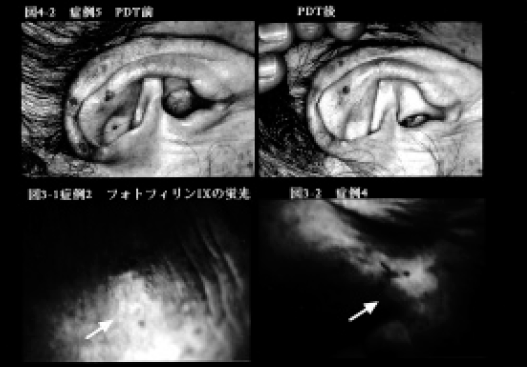

1)日光角化症 66~93歳の女性の顔面にみられた日光角化症に対してPDTを行った。図3-1には82歳女性のPDT 前の所見を示した。

2)菌状息肉症 1例の菌状息肉症(62歳、女性)の体幹に多発する紅斑性浸潤局面(図4-1)に対してPDTを試みた。

日光角化症では1~5回の照射で1週後に皮疹は1~6週で消失(図3-2)、菌状息肉症では2回の照射により4週後には色素沈着を残すのみとなった(図4-3)。6カ月後の現在いずれも再燃をみていない。日光角化症の一例でPDT後のアポトーシス発現を検討した結果(Apotosis Detection Kit、宝酒造使用)、PDT 施行部にアポトーシス陽性細胞が観察されたが、染色態度は均一でなく、なお慎重な検討が必要と思われた。